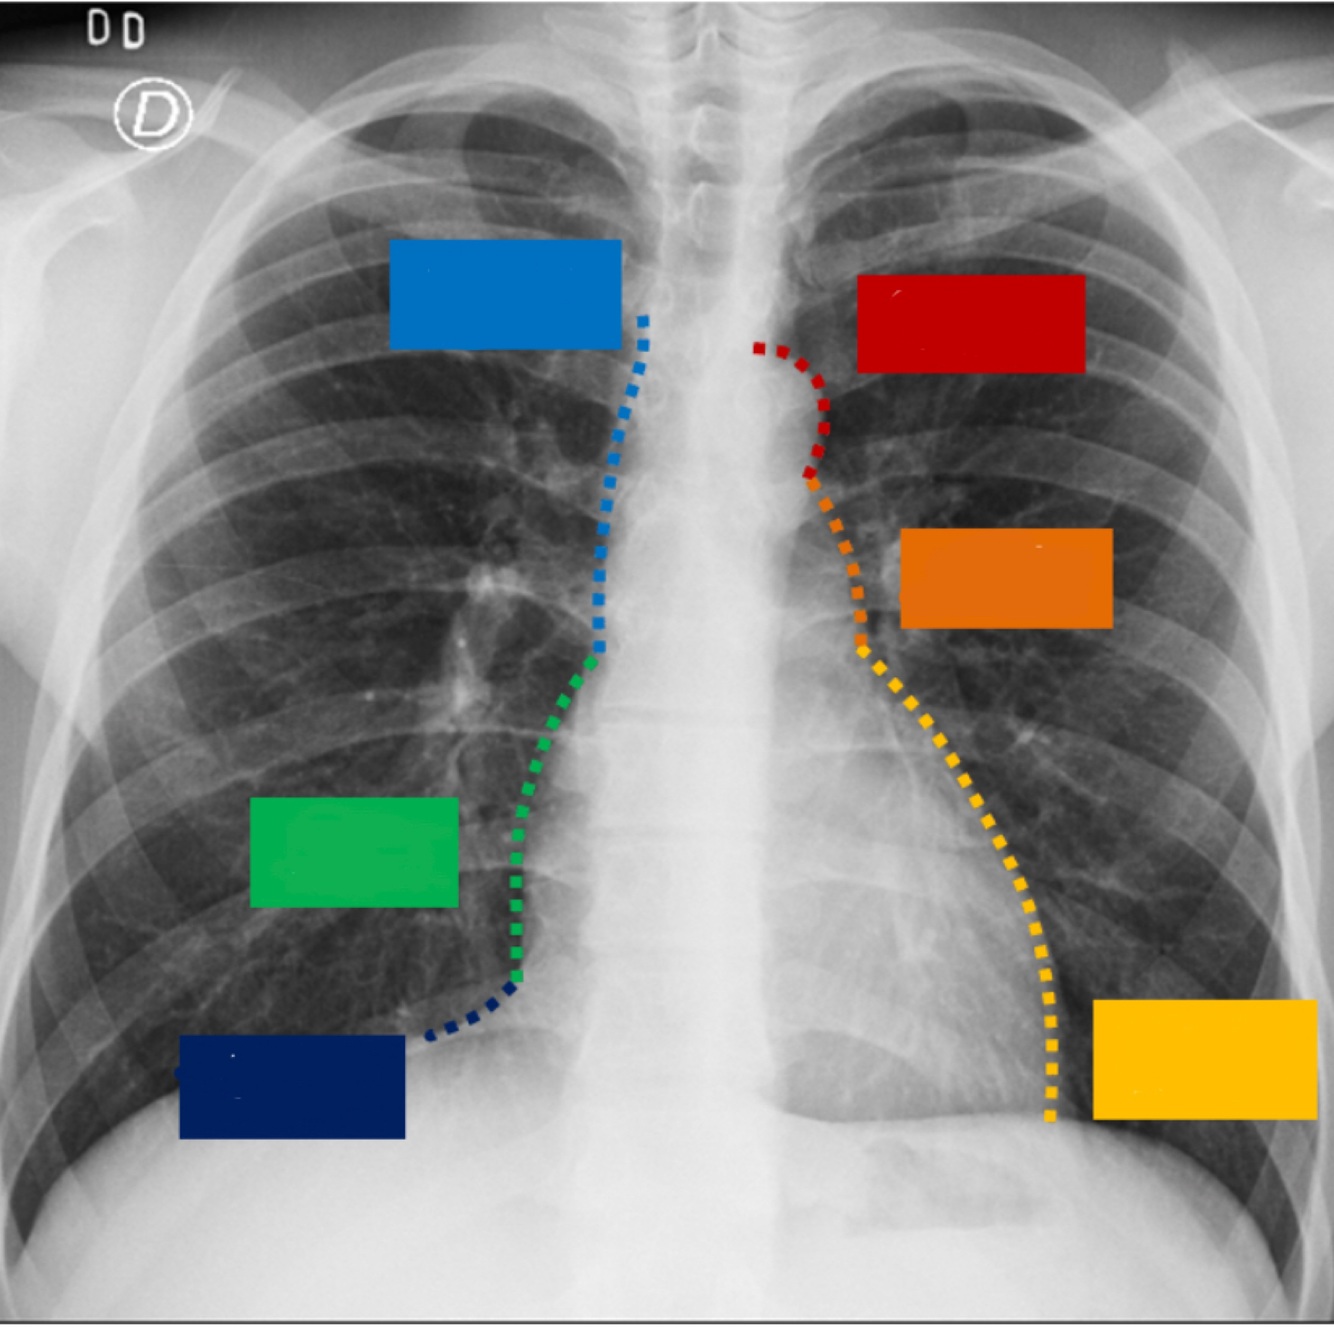

23

Describe el perfil cardiaco

24